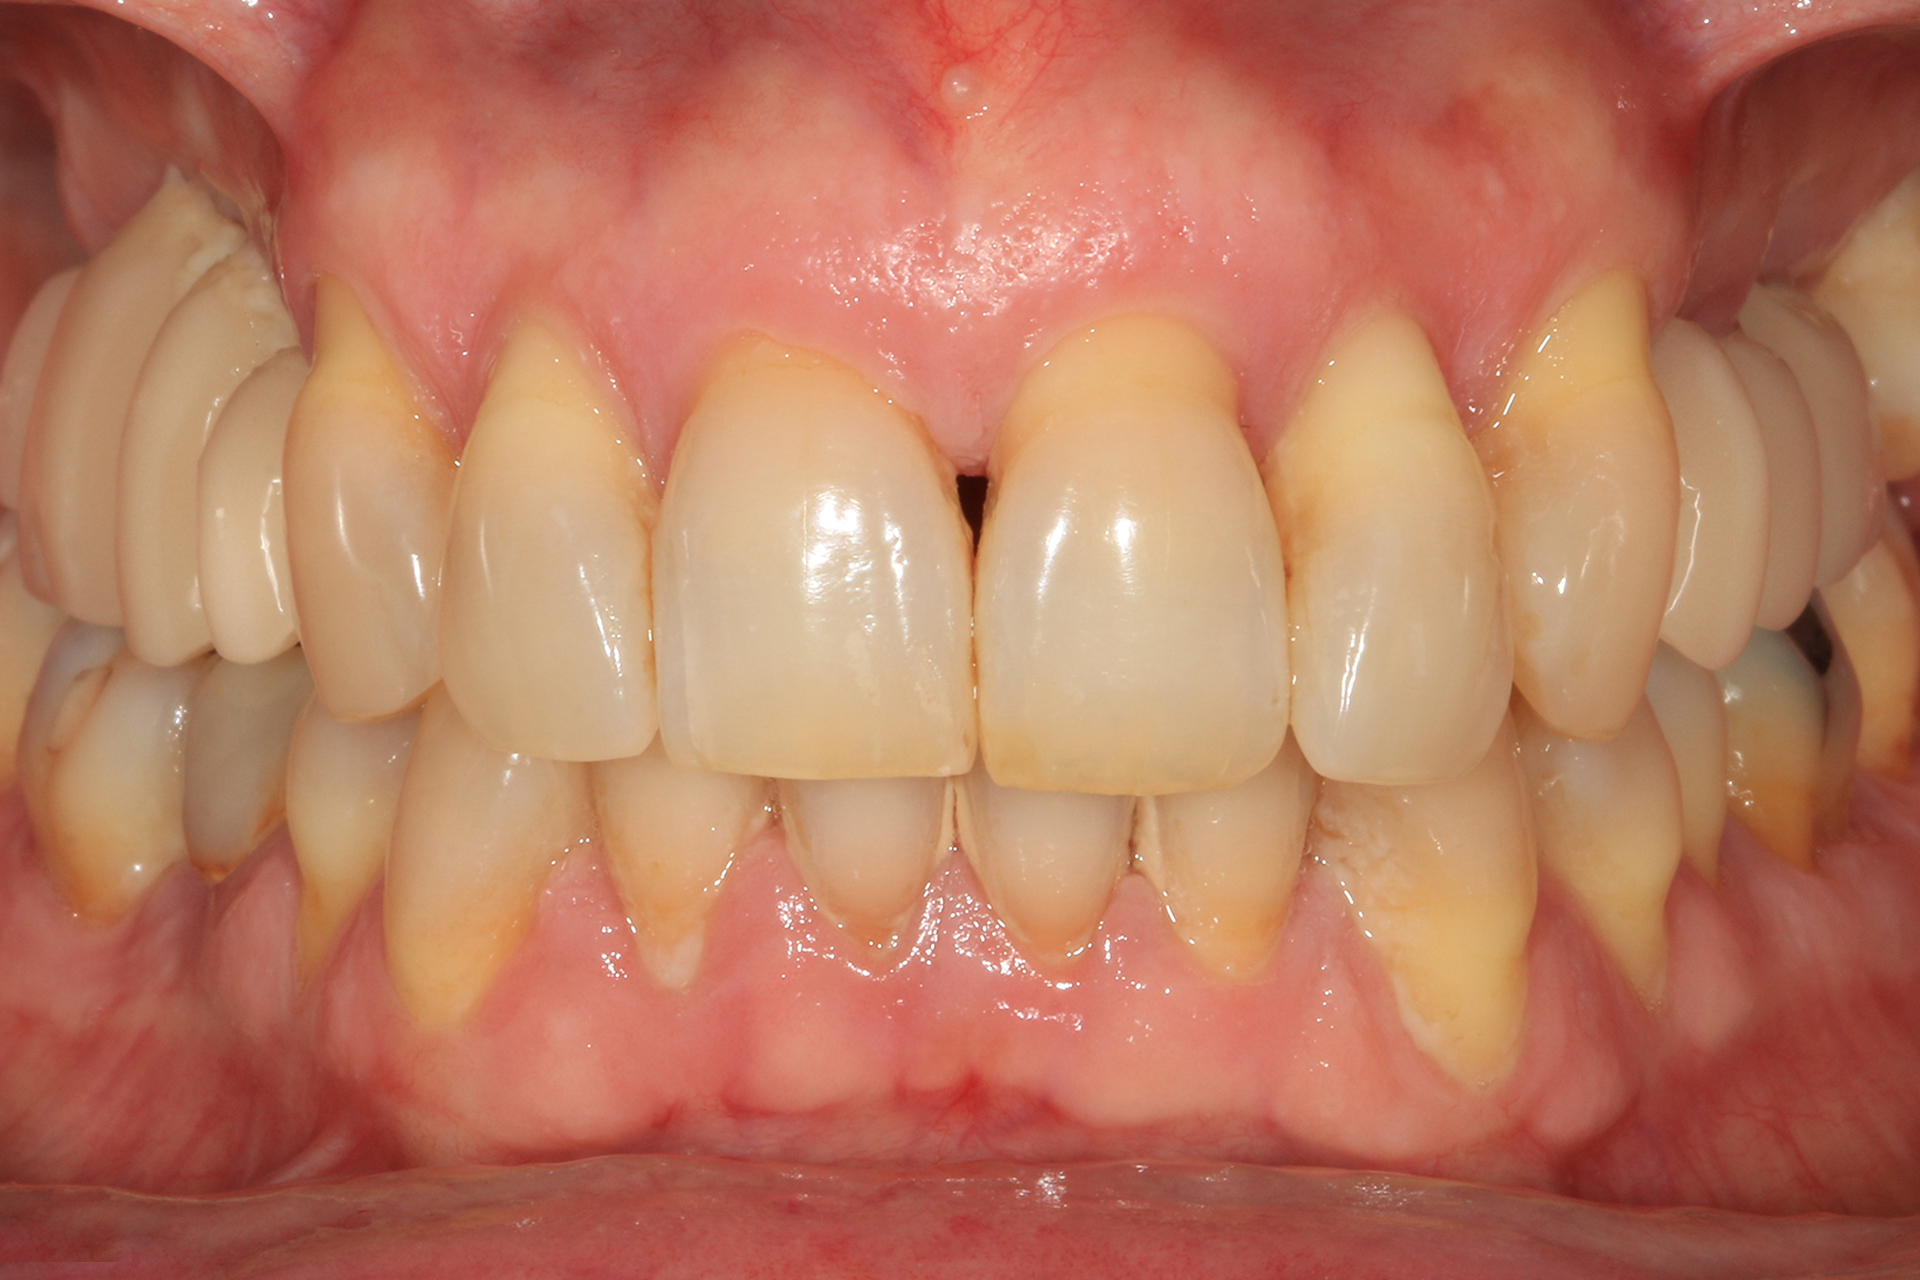

Métodos: Se llevó a cabo un caso clínico en una paciente de 40 años con fracaso de restauración fija dentosoportada en el incisivo central superior izquierdo, asociado a caries radicular subgingival con mal pronóstico restaurador. Tras la evaluación clínica y radiográfica, se indicó la exodoncia atraumática del diente afectado. Inmediatamente después, se realizó la colocación de un implante postextracción. El defecto periimplantario (gap) fue rellenado con un xenoinjerto óseo bovino. De forma simultánea, se llevó a cabo un injerto de tejido conectivo con el objetivo de optimizar el volumen y la estabilidad de los tejidos blandos periimplantarios. Se procedió a la colocación de una restauración provisional inmediata atornillada, diseñada para preservar el perfil de emergencia y guiar la cicatrización de los tejidos periimplantarios. Tras un periodo de cicatrización de cuatro meses, se colocó la restauración definitiva atornillada.

Resultados: El seguimiento clínico y radiológico evidenció una correcta osteointegración, estabilidad de los tejidos periimplantarios y un resultado estético satisfactorio, mantenido a los cuatro años.